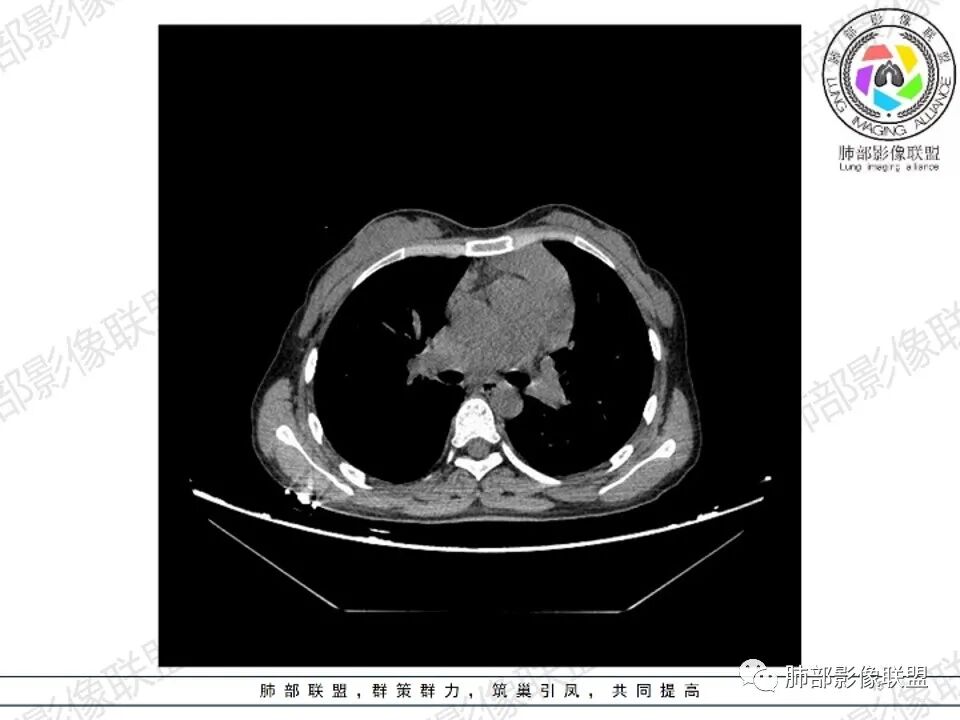

女,27,间断头晕、乏力3年,左眼视物模糊2月。贫血。胸部CT:前纵隔不规则肿块,多结节融合,边界不清,沿主动脉及肺动脉间隙生长,平扫密度欠均匀,增强扫描可见多发低密度坏死,纵隔血管供血穿行,腋窝多发大小不等淋巴结肿大。考虑恶性病变,胸腺癌?肉瘤?淋巴瘤?鉴别胸腺瘤、结节病等。

临床:年轻女性,慢性病程,多系统病变,头晕,贫血,视物模糊。

CT:定位纵膈病变,前中纵隔多发肿块,质软,塑形,密度不均匀,边界清楚。增强不均匀强化,坏死边界清楚,血管漂浮征。双侧腋下多组淋巴结肿大,明显异常强化。

考虑淋巴瘤可能。